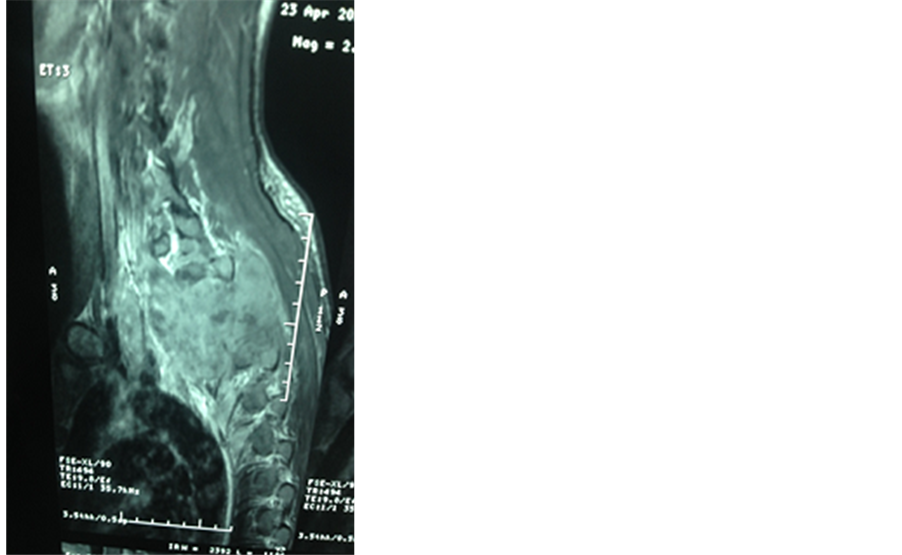

MRI of the spine showed a spinal cord compression due to bone and epidural tumoral lesions of the posterior wall of the D1 to D5 thoracic vertebras (Figure 1).

Figure 1. T1 and T2 magnetic resonance imaging (MRI) images show cord compressing tumoral mass at D1 to D5 thoracic vertebras.